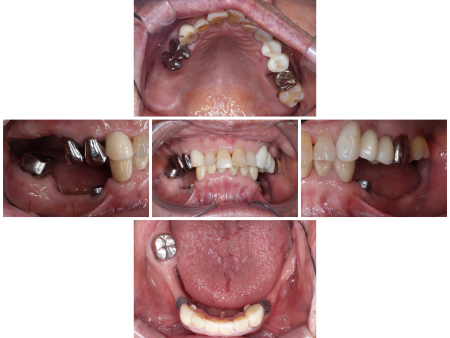

1988年から来院中の患者様より「入れ歯が破損したので直したい」とご相談いただきました。

拝見したところ、下左右の歯がない「欠損部」に部分入れ歯が装着されており、特に左下の人工歯は上の歯に強く当たっているため、かなりすり減っていました。

さらに左下の入れ歯と入れ歯を固定するためのマグネットも破損しています。

下の前歯6本(右犬歯/3番~左犬歯)は、上前歯と強く当たり著しく削れる「咬耗(こうもう)」が生じていました。下左右の奥歯がないため、唯一自分の歯で噛める前歯部分に負担がかかりすぎたことが咬耗の原因と考えられます。

また、咬耗により噛み合わせたときの上下の顎の垂直的距離である「咬合高径」が低くなり、特にマグネット部分の隙間が小さくなっていました。

この咬合高径の低さも、入れ歯が破損した理由の一つです。

入れ歯は何度か破折し修理していますが、今回修理したとしても、隙間の不足により再び壊れてしまうことが予想されました。そのためまずは、下前歯に被せ物を装着して咬合高径を高くし、欠損部の隙間を増やしてから入れ歯の厚みを確保する必要があると診断しました。

下の前歯6本(右犬歯~左犬歯)は審美性に優れ、強度もある人工ダイヤモンドを用いた被せ物「フルジルコニアクラウン」で咬合高径を高くし、その後入れ歯を修理する治療計画を提案し、同意いただきました。